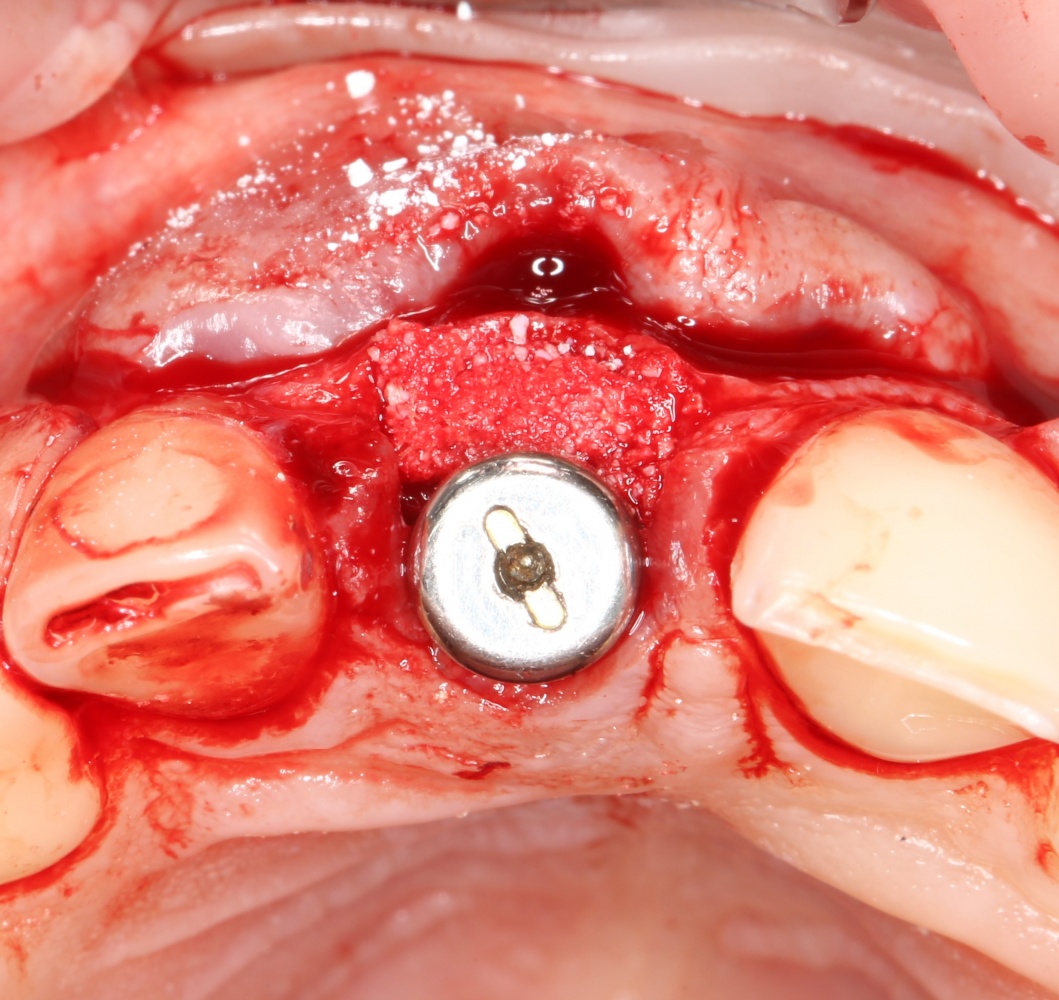

Все началось с воспаления, свищевого хода и удаления зуба:

Затем, мы готовим лунку и проверяем позиционирование импланта:

После чего аугментируем лунку. Для упаковки Bio-Oss Collagen очень удобно использовать аналоги имплантов:

Устанавливаем имплантат XiVE (Dentsply Implants):

Сразу на имплантат — временная коронка: